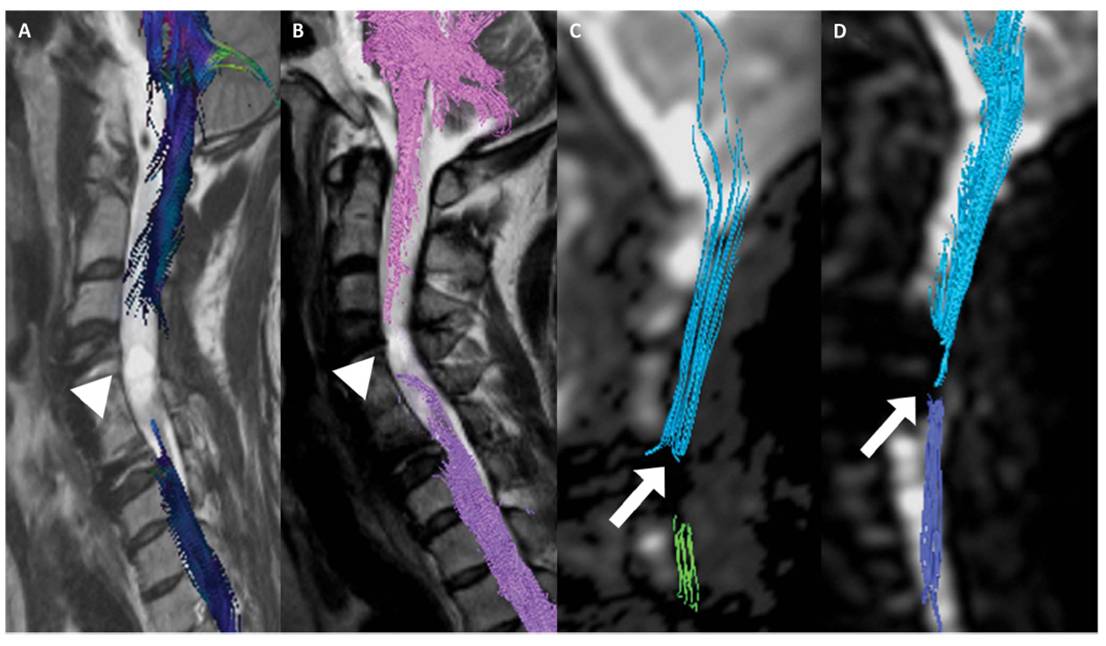

이어 “그러나 줄기세포치료제를 단회 투여했음에도 불구하고 호전된 환자의 척수 MRI 및 DTI 검사 결과 척수손상 부위에서 줄기세포치료 전에는 없던 섬유의 연속성(fibercontinunity)이 확인되는데 이는 줄기세포치료로 인한 신경재생 효과로 판단할 수 있다"고 말했다.

[환자의 MRI와 DTI검사결과다. 줄기세포치료제투여하기 전(A와C)에 비해 투여 후 6개월이 경과한 후(B와 D)에는끊어진 척수신경이 재생되었음을 확인할 수 있다.]

[환자의 DTI검사결과다. 줄기세포치료제 투여하기 전(A와C)에 비해 투여 후 6개월이경과한 후(B와 D)에는 끊어진 척수신경이 재생되었음을 확인할수 있다